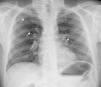

At the age of 47, he was referred to our hospital's outpatient cardiology clinic due to mild dilatation of the aortic root and ascending aorta detected on a transthoracic echocardiogram (Figure 1A). The aortic valve was tricuspid with mild central regurgitation, and the left ventricle presented normal dimensions, mild concentric hypertrophy and preserved systolic function (Figure 1B–D). Due to a poor suprasternal view, the aortic arch could not be observed. Blood pressure was 135/80 mmHg in both arms. Lower limb pulses were weakly palpable and blood pressure was significantly lower (80/60 mmHg), so aortic coarctation was considered. No cardiac, dorsal or abdominal murmurs were audible. On the 12-lead electrocardiogram he had incomplete right bundle branch block and left ventricular hypertrophy. Chest radiography showed normal cardiac silhouette and bilateral rib notching (Figure 2).

A careful physical examination provides the first clue to the diagnosis of IAA or aortic coarctation and is of utmost importance in all young adults with hypertension. Lower systolic blood pressure in the lower than in the upper limbs and/or a delay or decrease in amplitude of femoral pulses compared to brachial or carotid pulses should raise the suspicion of coarctation or interruption of the aorta. Unlike coarctation, in IAA there is no audible systolic murmur of blood flow across the constriction, because there is a complete interruption of flow between the proximal and distal parts of the aorta. However, continuous murmurs of the collateral vessels may be heard over the parasternal or scapular areas; occasionally, periscapular collaterals can be palpated. Notching on the underside of the ribs from collateral vessels may be apparent on chest radiography. The diagnosis of IAA must be confirmed with an imaging method, such as echocardiography, computed tomography, magnetic resonance imaging or conventional angiography.